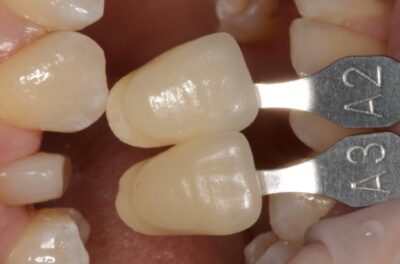

Специализация: терапия(эндодонтия), ортопедия, имплантология.